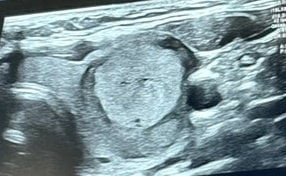

Pippa Collins-Gould's cancer scan. (Pippa Collins-Gould via SWNS)

Pippa turned to ChatGPT, inputting the results, which informed her she had been diagnosed with encapsulated angioinvasive follicular thyroid cancer.